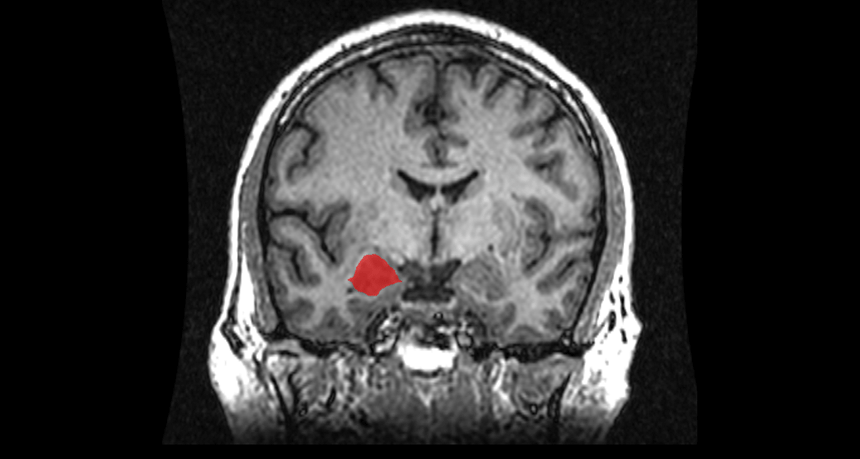

This is a slice of brain seen through a scan that looked through a person’s face and into their head. The right amygdala is highlighted in red.

Amber Rieder, Jenna Traynor, Geoffrey B Hall/Wikimedia Commons (CC0 1.0)

This part of the brain plays a role in memory, decision making and emotions, such as fear. Each person has an amygdala on either side of their head. They are located near the center of the brain a little above the ears. The amygdala gets its name from the Greek word “amygdalo.” It means “almond.” Each amygdala is shaped a little like the tasty nut.